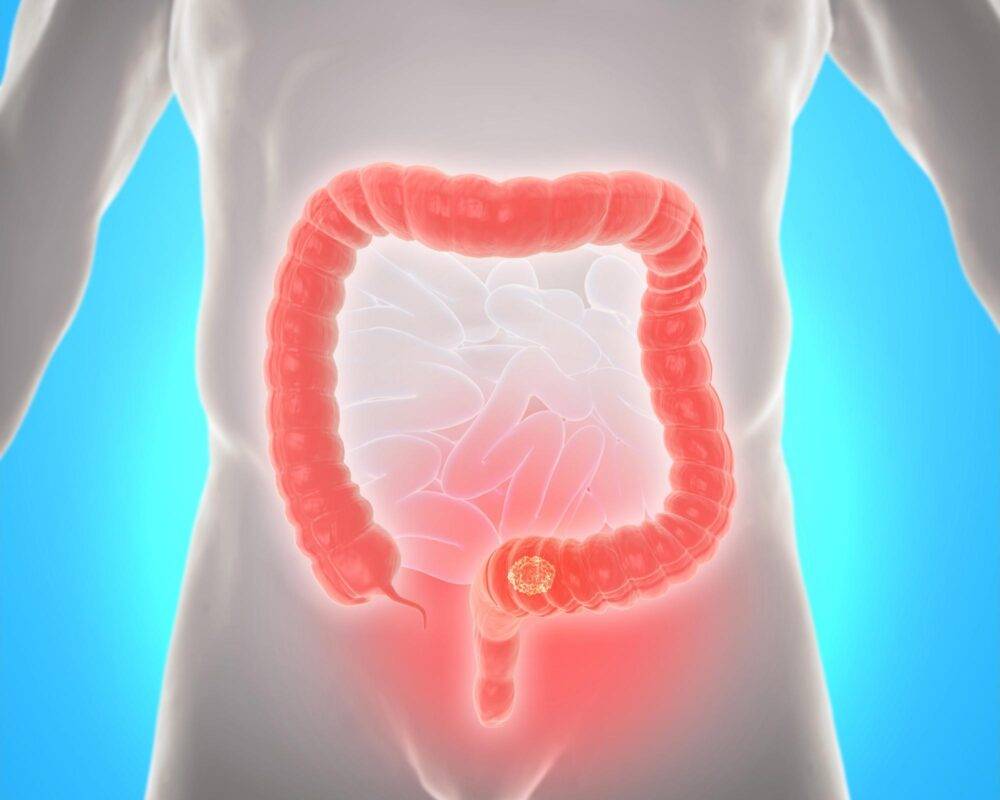

Colorectal (Colon) Cancer

The large intestine is the last part of the digestive tract. It has two components: the colon, which makes up the first six feet of the...